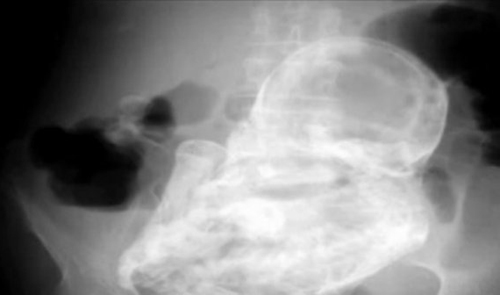

It was only when medics x-rayed her they discovered the calcified foetus or lithopaedian inside her body.

Lithopaedian, also known as stone baby, is a rare syndrome that can occur when the foetus implants outside the uterus.

If the baby becomes too large to be absorbed back into the body, it undergoes a process of mummification, with barriers of calcium protecting the mother from the decaying foetus.

The stone baby can then remain undiagnosed for decades. There are fewer than 300 cases reported in medical literature.